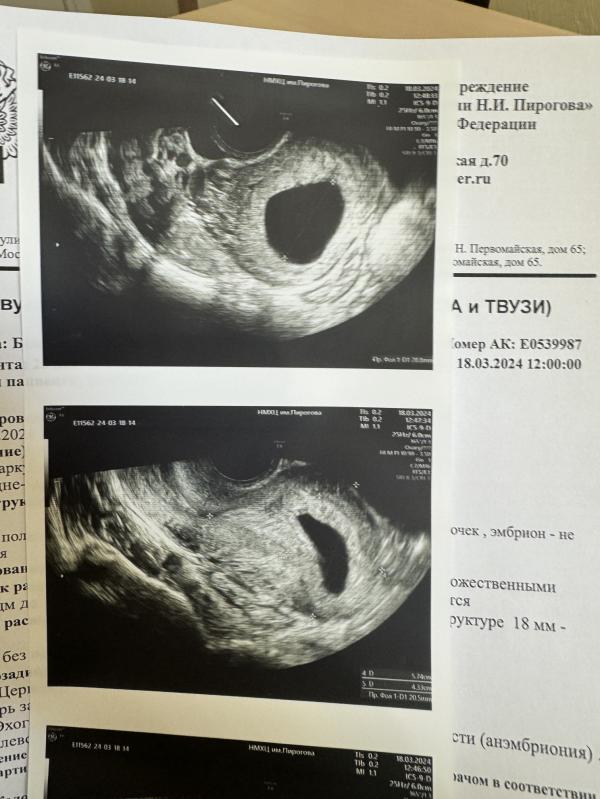

Сегодня была на узи повторно, результат печальный. Осмотрели 2 врача, на узи увидели плодное яйцо 28 мм. Эмбриона нет. Смысла ждать ещё неделю тоже нет.

У меня первая беременность - анэмбриония была летом… тоже хгч рос и был огромный, ждали долго изза хгч, но в итоге эмбрион не появился и плодное яйцо начало деформироваться.